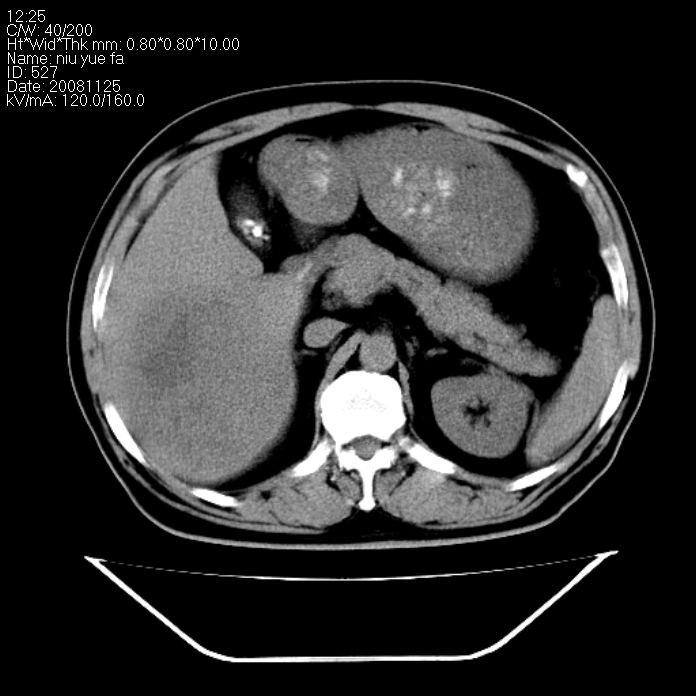

巨块型肝癌,坏死,出血;胆囊结石

1)考虑肝右叶巨块型肝癌并坏死、出血;建议行ct增强扫描检查进一步明确诊断。2)胆囊结石,胆囊炎。

考虑肝右叶巨块型肝癌并坏死、出血;建议行ct增强扫描。胆囊结石。

肝右叶巨块型肝癌并坏死、出血;胆囊结石,胆囊炎。